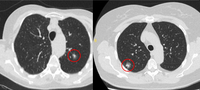

Tomografia computadorizada (TC) mostrando duas áreas (círculos vermelhos) de impactação mucoide dos brônquios subsegmentares do lobo superior esquerdo, resultando em aparência que mimetiza um nódulo

Do acervo de Dr. George Tsaknis, MD, PhD, FRCP (Londres), MRQA, MAcadMEd, PGCert; usado com permissão